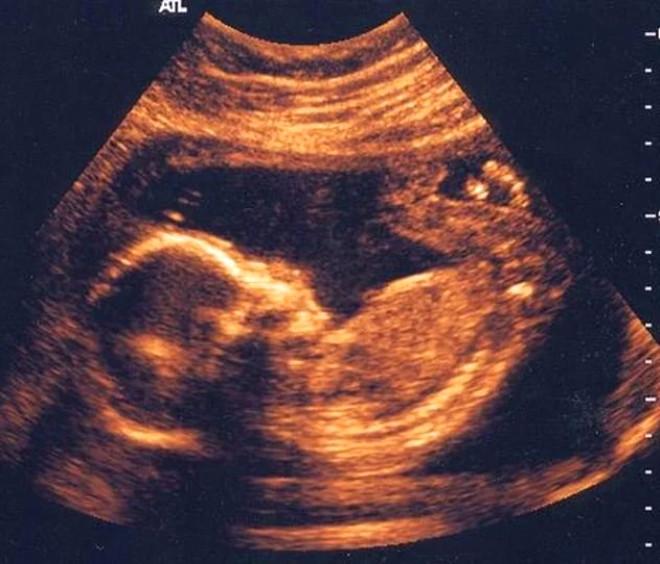

Erkek Bebek Ultrasonda Nasıl Görünür Ultrasonda Erkek

Bebeğin Cinsiyeti En Erken Ne Zaman Belli Olur?

Gebelikte Cinsiyet Kaçıncı Haftada Belli Olur? Nasıl